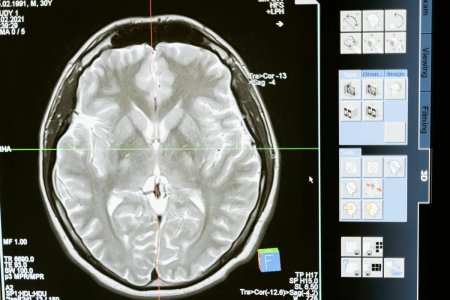

A growing concern for aging populations and future generations. Image Source: Pexels / MART PRODUCTION.